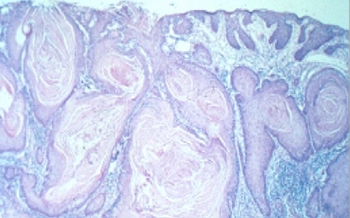

• Trinity researchers awarded 2.9 million for oral and oesophageal cancer research

Researchers in Trinity’s School of Biochemistry and Immunology and School of Dental Science have been awarded €2.9 million Horizon 2020 funding.